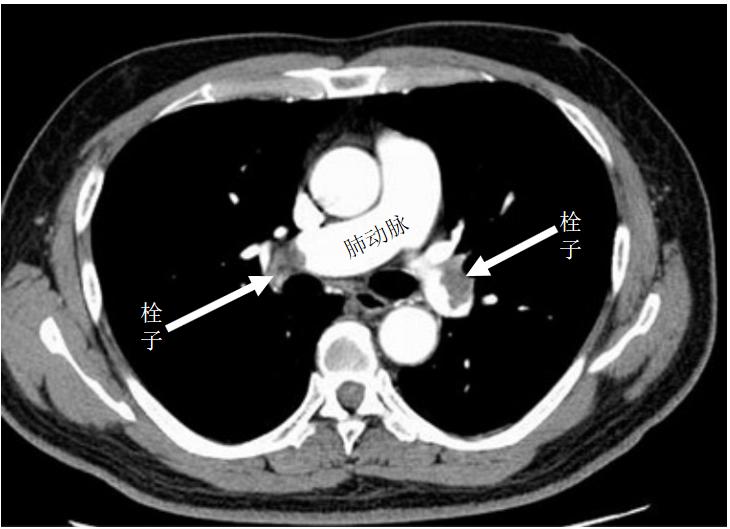

当血栓堵塞心脏的冠状动脉,就会引起心肌缺血,造成心绞痛、心肌梗死;堵住颅内动脉,就会引起脑梗死,出现中风偏瘫等诸多症状;堵住肠道的血管,就会造成肠缺血、肠坏死、肠穿孔;堵住下肢动脉,自然会引起下肢的缺血,同样会引起肢体的缺血坏死,最终可能造成截肢。静脉内的血栓引起缺血的机会不多,但因为阻挡了血液回流,多引起下肢水肿、肠道淤血水肿、腹水等,然而更严重的是,静脉血栓可随血流回流到心脏,再随血流堵塞肺动脉,从而引起“肺栓塞”。

大面积的肺梗死同样可引起猝死